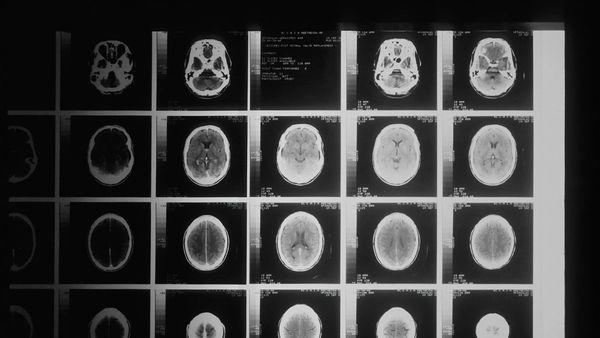

إن العقل البشري، على الرغم من أن وزنه لا يتجاوز ٣ أرطال، يجسد قدرات هائلة، وينظم أفكارنا، وعواطفنا، وأفعالنا الجسدية. إنها شبكة معقدة من ملايين الخلايا العصبية، والتي إذا تعطلت، يمكن أن تؤدي إلى ضعف كبير في الحركة والإحساس والعمليات المعرفية. وللحفاظ على صحة الدماغ ووظائفه المثلى، يوصى باستخدام عدة استراتيجيات.